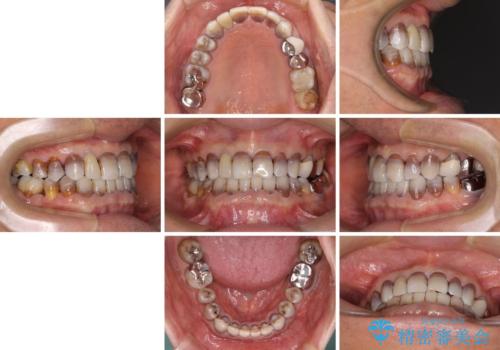

- 前歯のクロスバイトを気にして来院された患者様です。

骨格的に下顎が前方位ではありますが、歯並びが改善されれば正常咬合となることが分かったため、インビザラインを用いて咬み合わせを改善していくこととしました。

インビザラインは四六時中上下のマウスピースを介した咬合状態となるため、治療過程にて奥歯が接触しないという状態が続くことがあります。

奥歯の非接触は機能面において大きな障害であるため、この問題を解決しない限り矯正治療を終えることはできません。

インビザラインでの矯正治療が長期化してしまう要因の1つです。